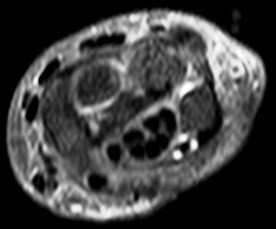

ECU6.jpg